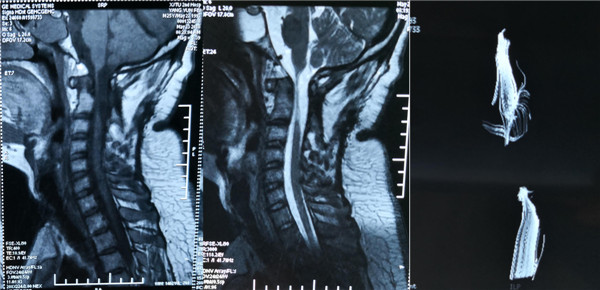

患者术前影像 颈1-3损伤 高位截瘫